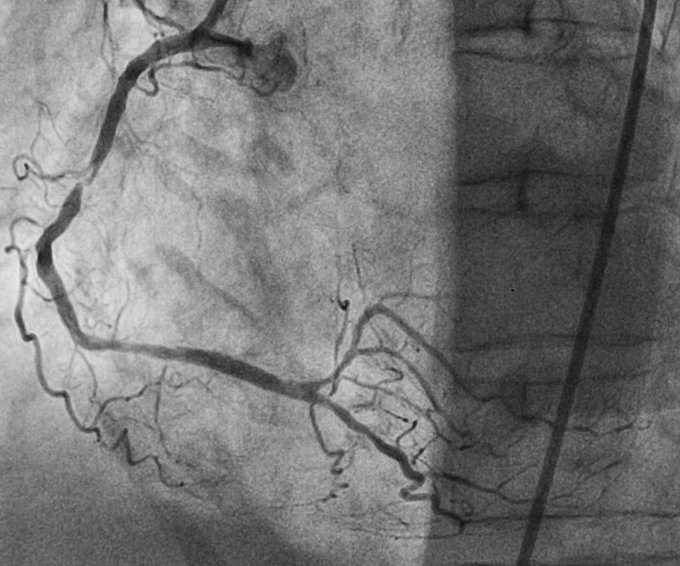

Ein sehr dünner Draht wird durch die Engstelle oder den Verschluss des Herzkranzgefäßes geführt. Dann wird ein Ballonkatheter in die Engstelle gelegt und mit Druck entfaltet. In den meisten Fällen muss noch eine Gefäßstütze (Stent) in das Herzkranzgefäß eingelegt werden, da das Ergebnis der Aufdehnung allein nicht ausreichend ist. Hierbei setzen wir zunehmend Stents ein, die mit einem Medikament beschichtet sind und das Risiko einer erneuten Gefäßverengung im Stentbereich reduzieren. Dabei richten wir uns nach den Leitlinien der deutschen und europäischen Fachgesellschaften. Bei stark verkalkten Gefäßen setzen wir einen Bohrer (Rotablator) ein, um so einen glatten Kanal für die Stentimplantation zu schaffen. Nach der Untersuchung wird der Patient in einem speziellen Überwachungszimmer bis zum nächsten Tag versorgt.